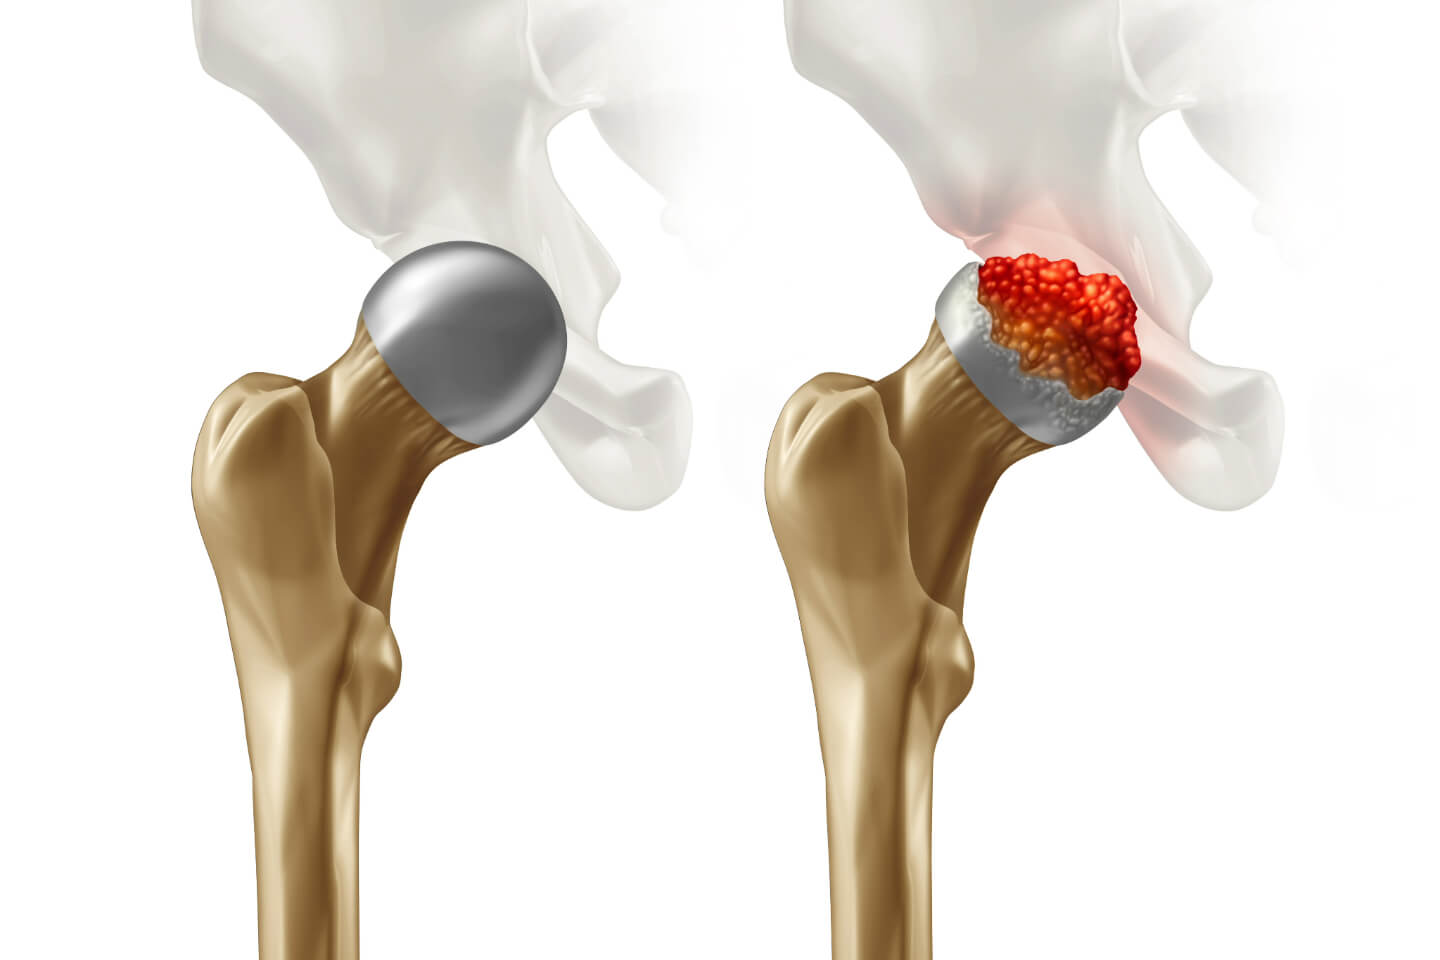

Reoperation on previous hip replacements that have worn out, failed, or become loose.

At Gifford Orthopaedics, we specialize in advanced treatments for hip and knee conditions, helping patients regain mobility and live without pain. Our services range from minimally invasive procedures to total joint replacements, all tailored to meet your unique needs.